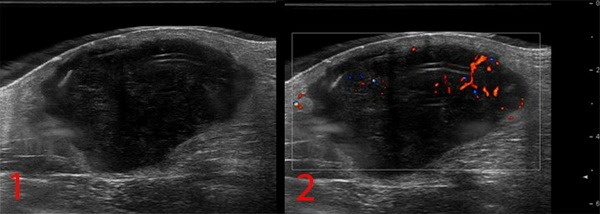

- УЗИ опухолей мягких тканей. Это метод диагностики как первичного очага, так и поражения региональных зон. Позволяет определить границы опухоли, связь с окружающими органами, структуру опухоли;

Рисунок №1. Саркома мягких тканей бедра. УЗ-картина в серошкальном и сосудистом режимах визуализации